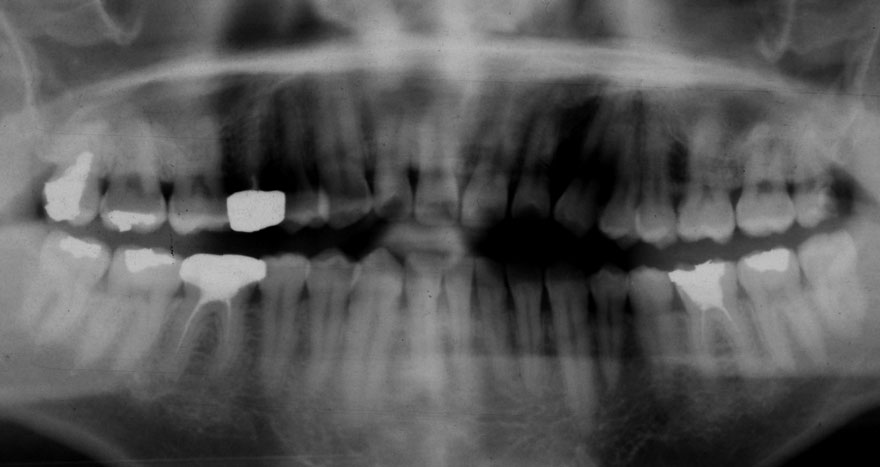

初診時 28歳 男性 平均歯槽骨喪失量:2.35mm

河田歯科医院

30年後 58歳

平均歯槽骨喪失量:3.88mm

22年間喪失量:-1.53mm

年間喪失速度:-0.05mm

(ケア頻度:2.80ヵ月ごと)